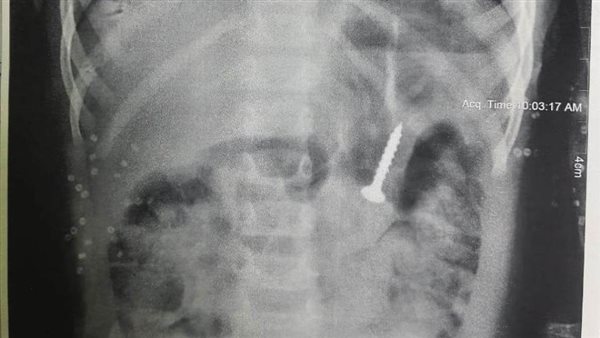

استخراج "مسمار" من معدة طفلة بمستشفى المنصورة التخصصي

تمكن فريق طبي بمستشفى المنصورة التخصصي، من استخراج "مسمار" من معدة طفلة رضيعة، بعدما ابتلعته عن طريق الخطا، وذلك دون تدخل جراحي.

وقال المستشفى في بيان صادر عنه، إن وحدة الجهاز الهضمي ومناظير الأطفال استقبلت طفلة تبلغ من العمر عامين، مصابة بحالة إعياء، وبعد عمل أشعة على المعدة تبين وجود جسم غريب "مسمار".

وأضاف البيان، أن الطفلة ابتلعت الجسم بالخطأ، وجرى استخراجه باستخدام تقنية المنظار دون تدخل جراحي، ووضع الحالة تحت الملاحظة.